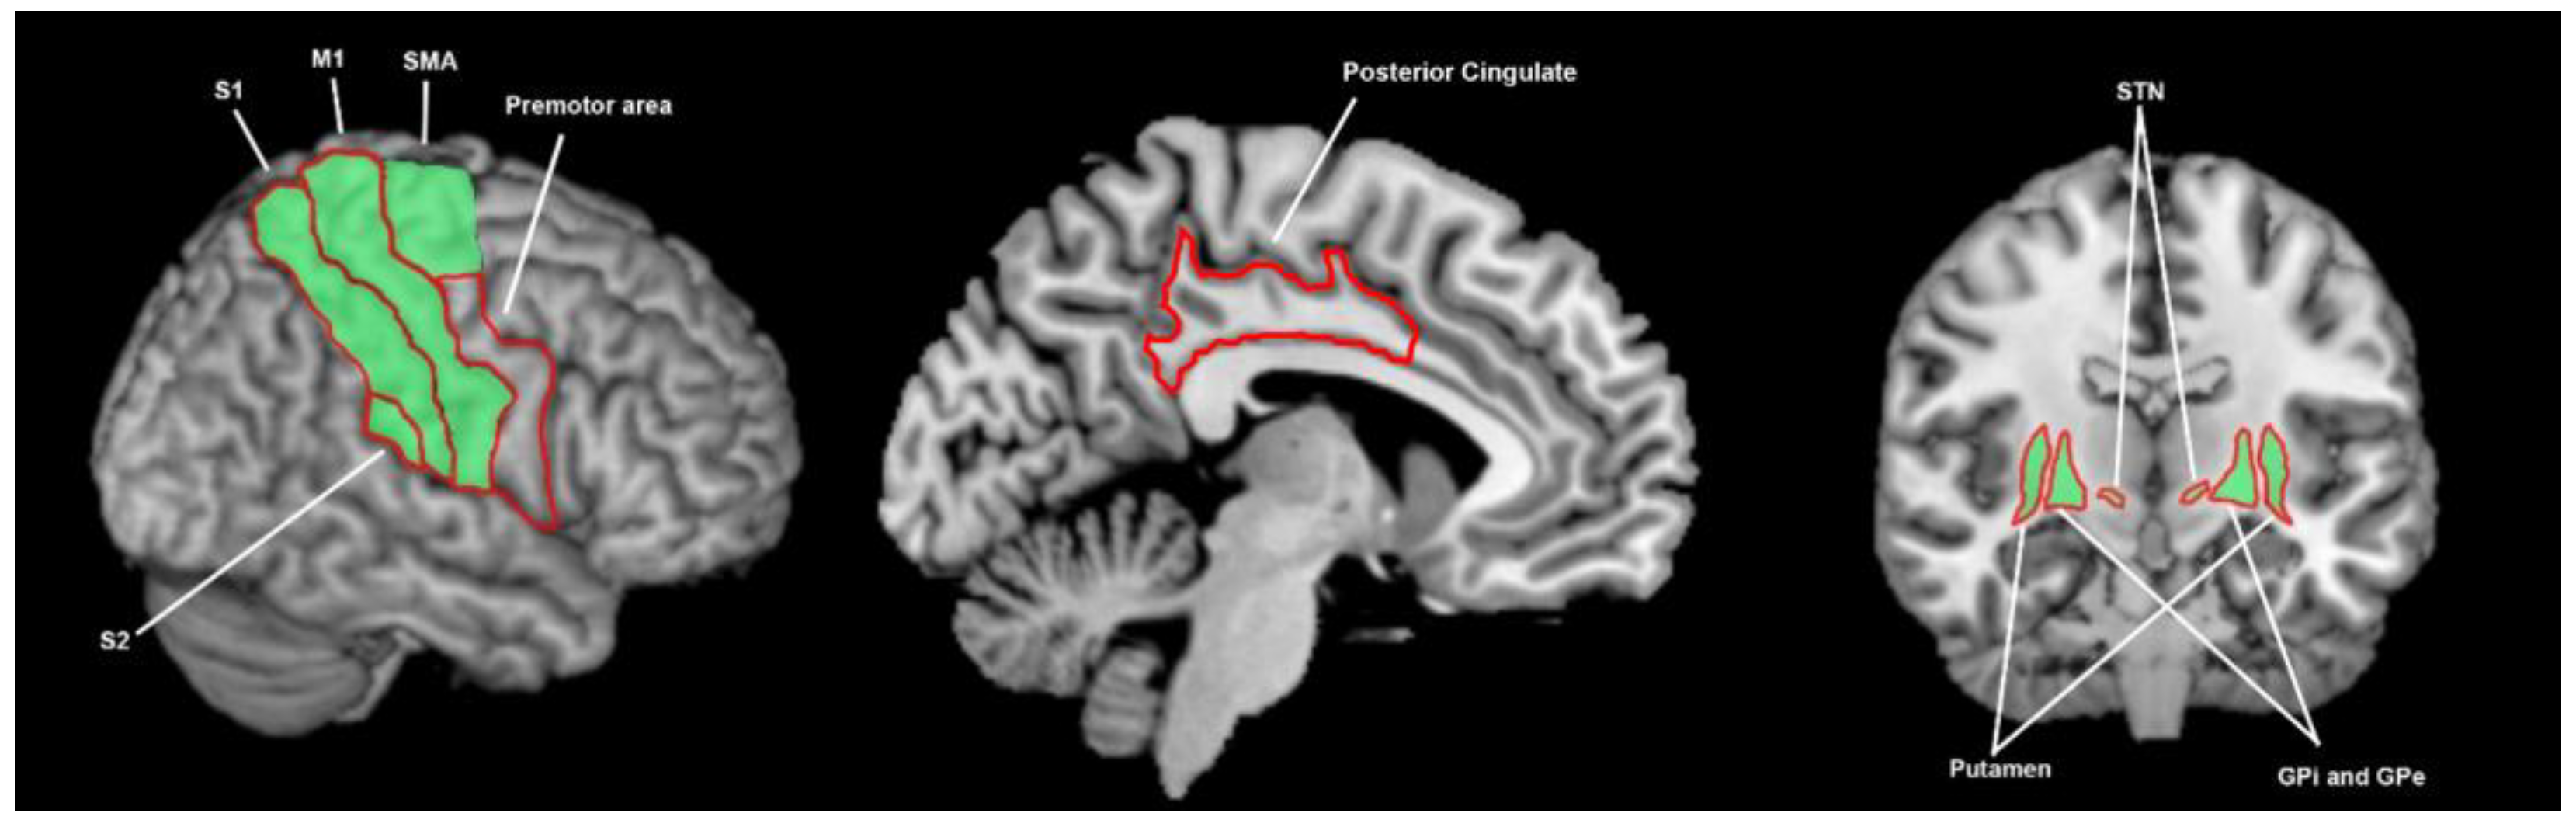

3.3.7. What Brain Areas Are Involved in Tactile Processing in Healthy Cohorts?

3.3.8. What Brain Areas Are Found to Function Abnormally during Tactile Processing in Patients with Parkinson’s Disease?

3.3.9. What Brain Areas Are Involved in Proprioceptive Processing in Healthy Cohorts?

3.3.10. What Brain Areas Are Found to Function Abnormally during Proprioceptive Processing in Patients with Parkinson’s Disease?

3.4. The Breadth of Sensory Response and Multisensory Response of the Basal Ganglia

4.1. What Brain Areas Are Involved in Sensory Processing, What Are the Abnormalities in Parkinson’s Disease, and What Is the Importance of the Basal Ganglia?